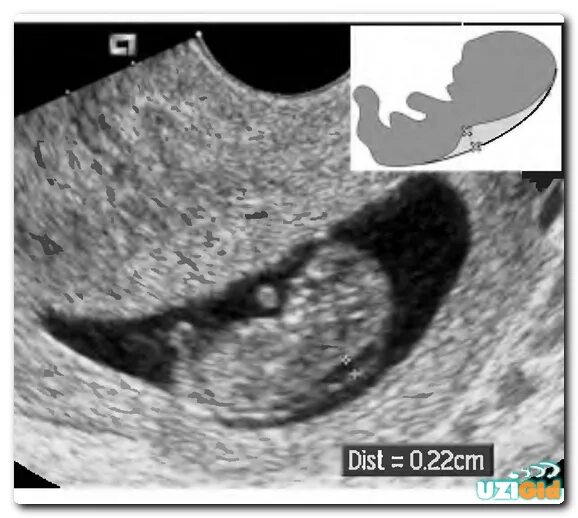

Воротниковое пространство 5